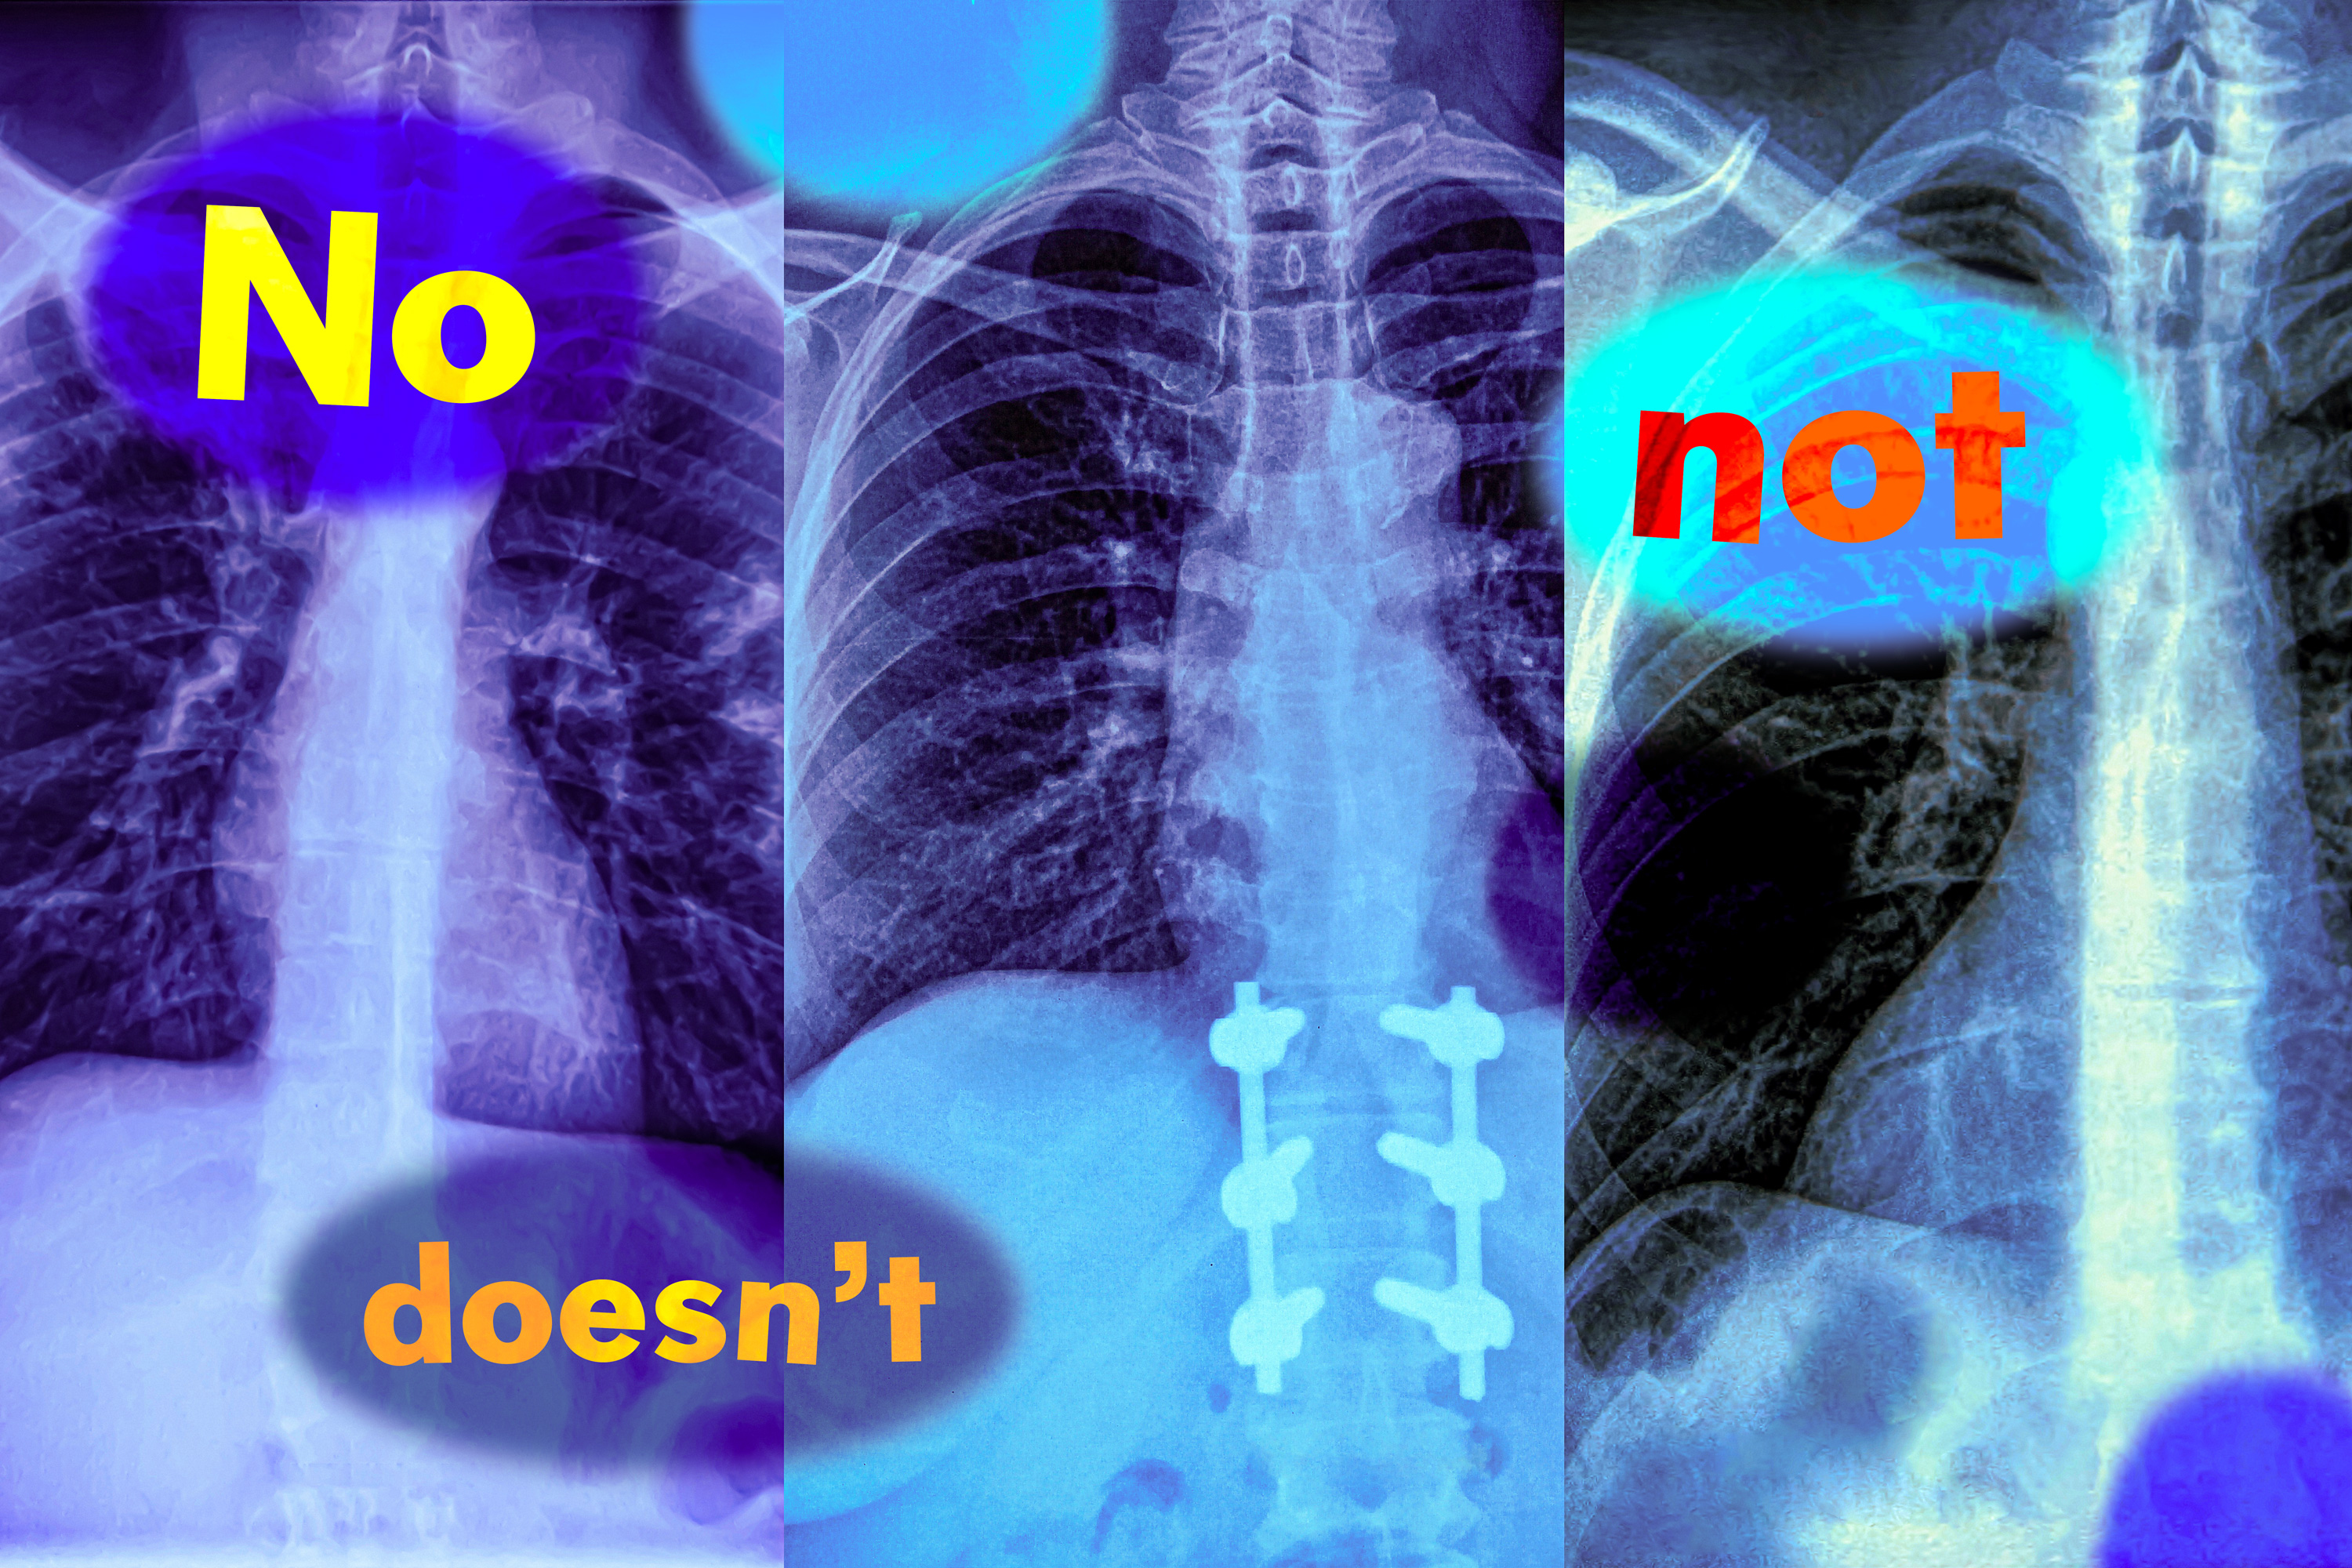

Study shows vision-language models can’t handle queries with negation words

Words like “no” and “not” can cause this popular class of AI models to fail unexpectedly in high-stakes settings, such as medical diagnosis.